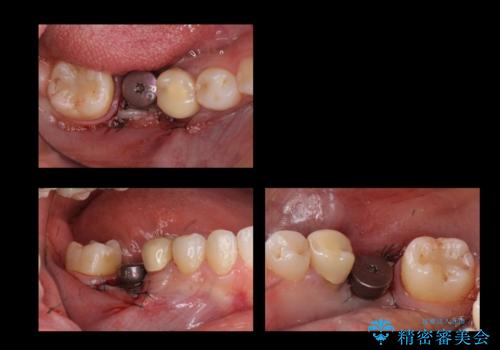

奥歯のインプラント

- 右下6番が保存不可能だったため、やむなく抜歯しました。

インプラント治療をご希望されたため、植立を行いました。

インプラントを入れる際、部分的に骨を増やす処置を行っています。